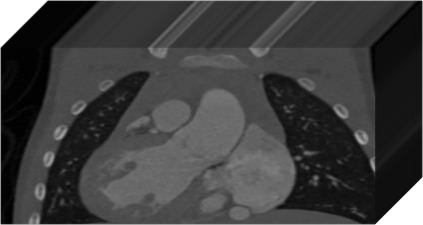

The success of deep learning heavily depends on the availability of large labeled training sets. However, it is hard to get large labeled datasets in medical image domain because of the strict privacy concern and costly labeling efforts. Contrastive learning, an unsupervised learning technique, has been proved powerful in learning image-level representations from unlabeled data. The learned encoder can then be transferred or fine-tuned to improve the performance of downstream tasks with limited labels. A critical step in contrastive learning is the generation of contrastive data pairs, which is relatively simple for natural image classification but quite challenging for medical image segmentation due to the existence of the same tissue or organ across the dataset. As a result, when applied to medical image segmentation, most state-of-the-art contrastive learning frameworks inevitably introduce a lot of false-negative pairs and result in degraded segmentation quality. To address this issue, we propose a novel positional contrastive learning (PCL) framework to generate contrastive data pairs by leveraging the position information in volumetric medical images. Experimental results on CT and MRI datasets demonstrate that the proposed PCL method can substantially improve the segmentation performance compared to existing methods in both semi-supervised setting and transfer learning setting.